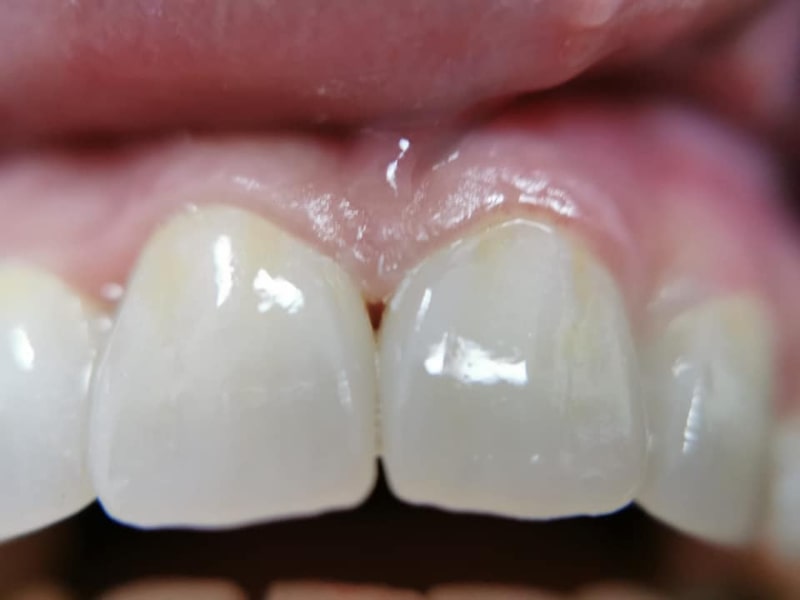

Punte Ceramică